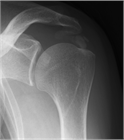

1. 肩関節の痛みの原因として、腱板断裂、石灰性腱炎、凍結肩(五十肩、肩関節周囲炎)、変形性関節症を想起すべきである(推奨度1)

1. 肩の痛みを訴える患者で、①棘上筋の筋力低下、②外旋筋の筋力低下、③インピンジメント徴候、の3つがそろっていれば98%の確率で腱板断裂と診断できる(推奨度2)